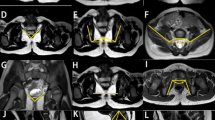

The present study demonstrates the clinical experience of pelvic floor stimulation using percutaneous implantable electrodes and implantable electrical stimulator for the treatment of reflex urinary incontinence in patients with spinal cord injury. Pelvic floor stimulation was carried out on six paraplegic patients who had urinary incontinence from an overactive bladder. After the percutaneous implantation of a pair of electrodes, chronic stimulation was carried out by employing an implanted receiver or an external pulse regulator. Within 4 to 16 weeks of electrical stimulation urinary incontinence was improved in four of the six patients. In two of these six patients, incontinence was completely abolished subjectively. Urodynamic investigations demonstrated an increased volume at the first unstable contraction (P<0.01) in all of the patients. Inhibition of detrusor overactivity was obtained from this procedure. The stimulation effect appeared to be constant during chronic stimulation. This new procedure probably provides a stable and reliable stimulation effect for long term treatment, and may be an alternative treatment for previous external electrical pelvic floor stimulation.

Ishigooka M et al. A technique of percutaneous implantation for electrical pelvic floor stimulation. Eur Urol 1993; 23: 413–416.

Ishigooka M et al. Electrical pelvic floor stimulation by percutaneous implantable electrode. Br J Urol 1994; 74: 191–194.